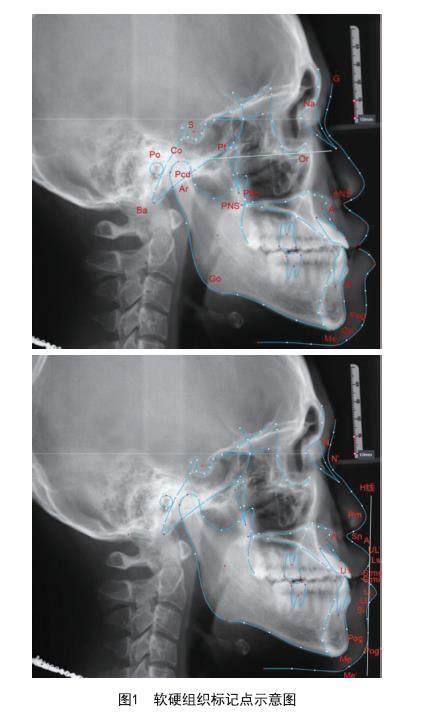

成人与青少年骨性Ⅲ类错牙合畸形患者掩饰性治疗后软硬组织和牙周情况对比分析

[摘要]目的:对成人与青少年骨性Ⅲ类错牙合畸形患者进行正畸掩饰性治疗,对比治疗前后软硬组织侧貌及牙周支持组织的变化,评价不同年龄组正畸治疗效果的差异。方法:选取2020年7月-2023年6月于无锡口腔医院就诊的40例符合研究标准的骨性Ⅲ类错牙合畸形患者,其中成年组20例,青少年组20例。两组均采取Damon Q自锁托槽矫治技术,期间未采用微种植体、前牵引面具等额外支抗装置,比较两组治疗前后软硬组织、牙周支持组织的测量值,评价不同年龄组的治疗效果及差异。(剩余13087字)